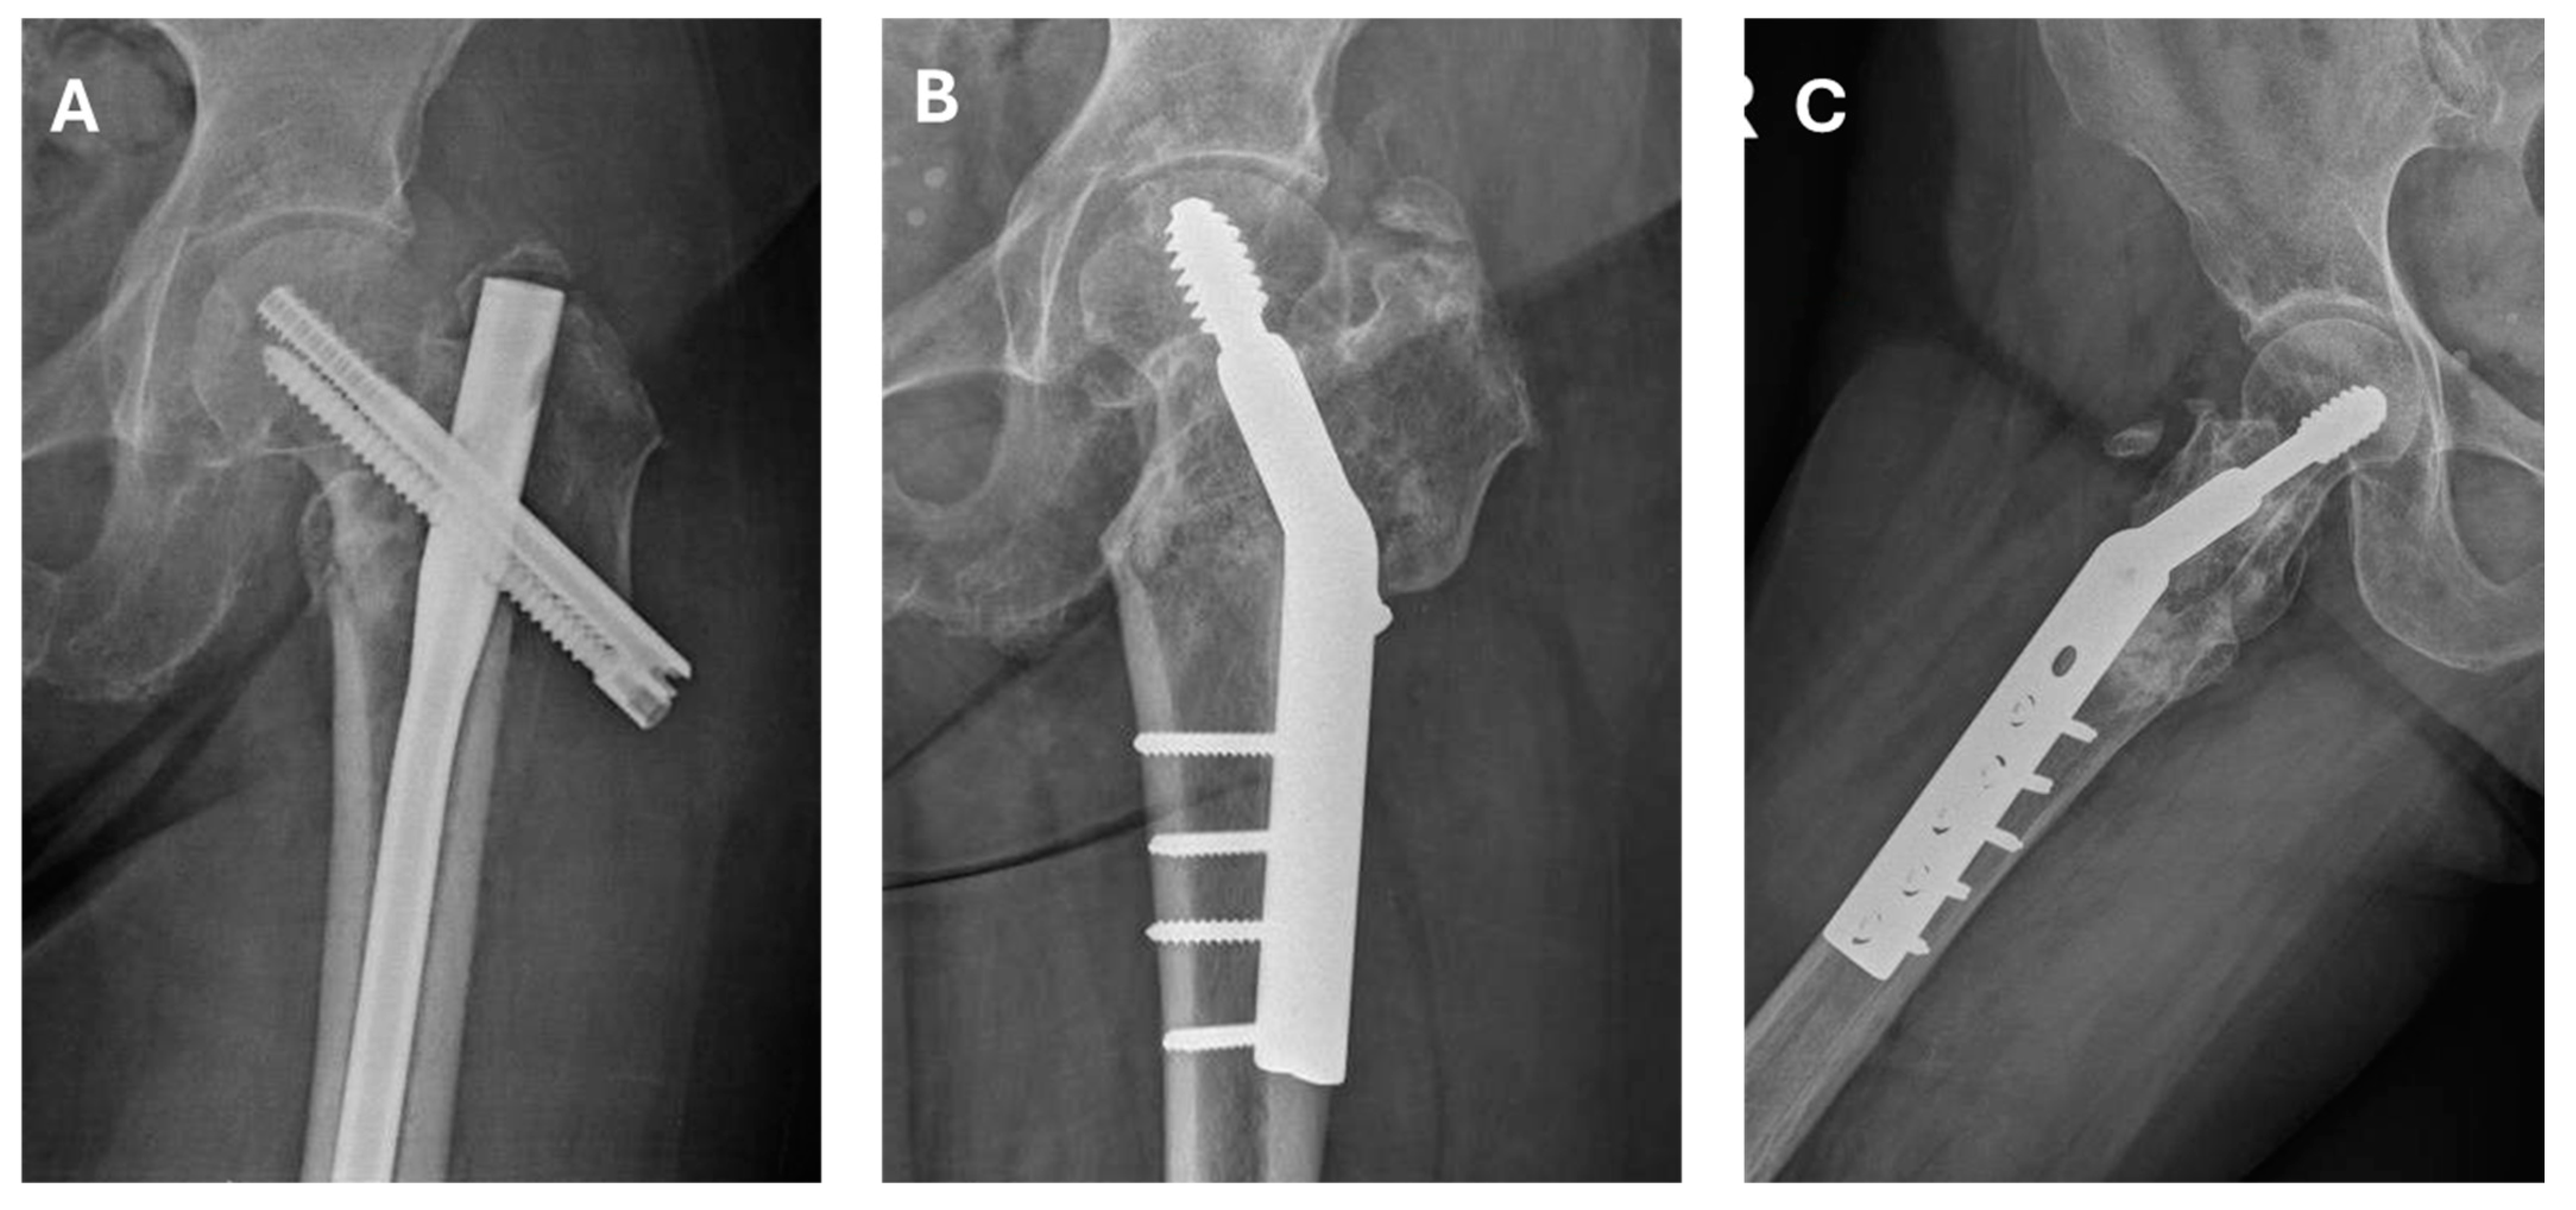

| Femoral neck angle post-surgery * | 142° | 150° | 150° | 147° | 145° | 146.8 (142–150) |

| Post-surgery offset (mm) * | 24 | 19 | 18 | 20 | 17 | 19.6 (17–24) |

| Vertical distance nonunion–head post-surgery (mm) * | 65 | 55 | 38 | 52 | 48 | 51.6 (38–65) |

| Postoperative leg lengthening (mm) * | 8 | 12 | 6 | 6 | 8 | 8 (6–12) |

| Time to union (months) | 4 | 6 | 6 | 5 | 4 | 5 (4–6) |

| Harris Hip Score post-surgery * | 96 | 96 | 88 | 90 | 88 | 90 (88–96) |